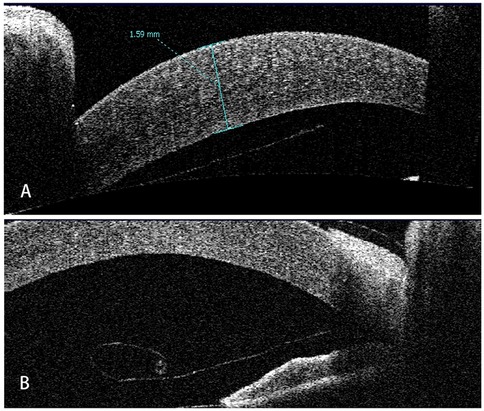

Seven children were reviewed in this study, including six boys and a girl. The mean age of the patients was 3.27 ± 4.73 (range: 0.33–13) years old. Five patients developed DMD after intraocular surgeries, of which four had DMD after glaucoma surgery and one following cataract surgery; two patients had DMD secondary to forceps-related birth injury. On average, DSAEK was performed 9.3 ± 13.0 (range: 1–36) weeks after the onset of DMD. Four out of the seven were aphakic eyes. According to AS-OCT or UBM, the central areas of the corneas were involved in all cases. Five had scrolled configuration, and the other two showed taut and stretched-out DM with tractional component (Figure 1). The specific demographics and clinical data are summarized in Table 1.

Figure 1. Representative AS-OCT images of pediatric DMD. (A) Case 1: tractional DMD with a taut, stretched-out DM. The traction may be caused by the inflammation and fibrosis after cataract surgery. (B) Case 2: DMD with scrolled configuration. After receiving Trabeculectomy, Descemet membrane broke off and detached into anterior chamber with the fractured end severely curled up.